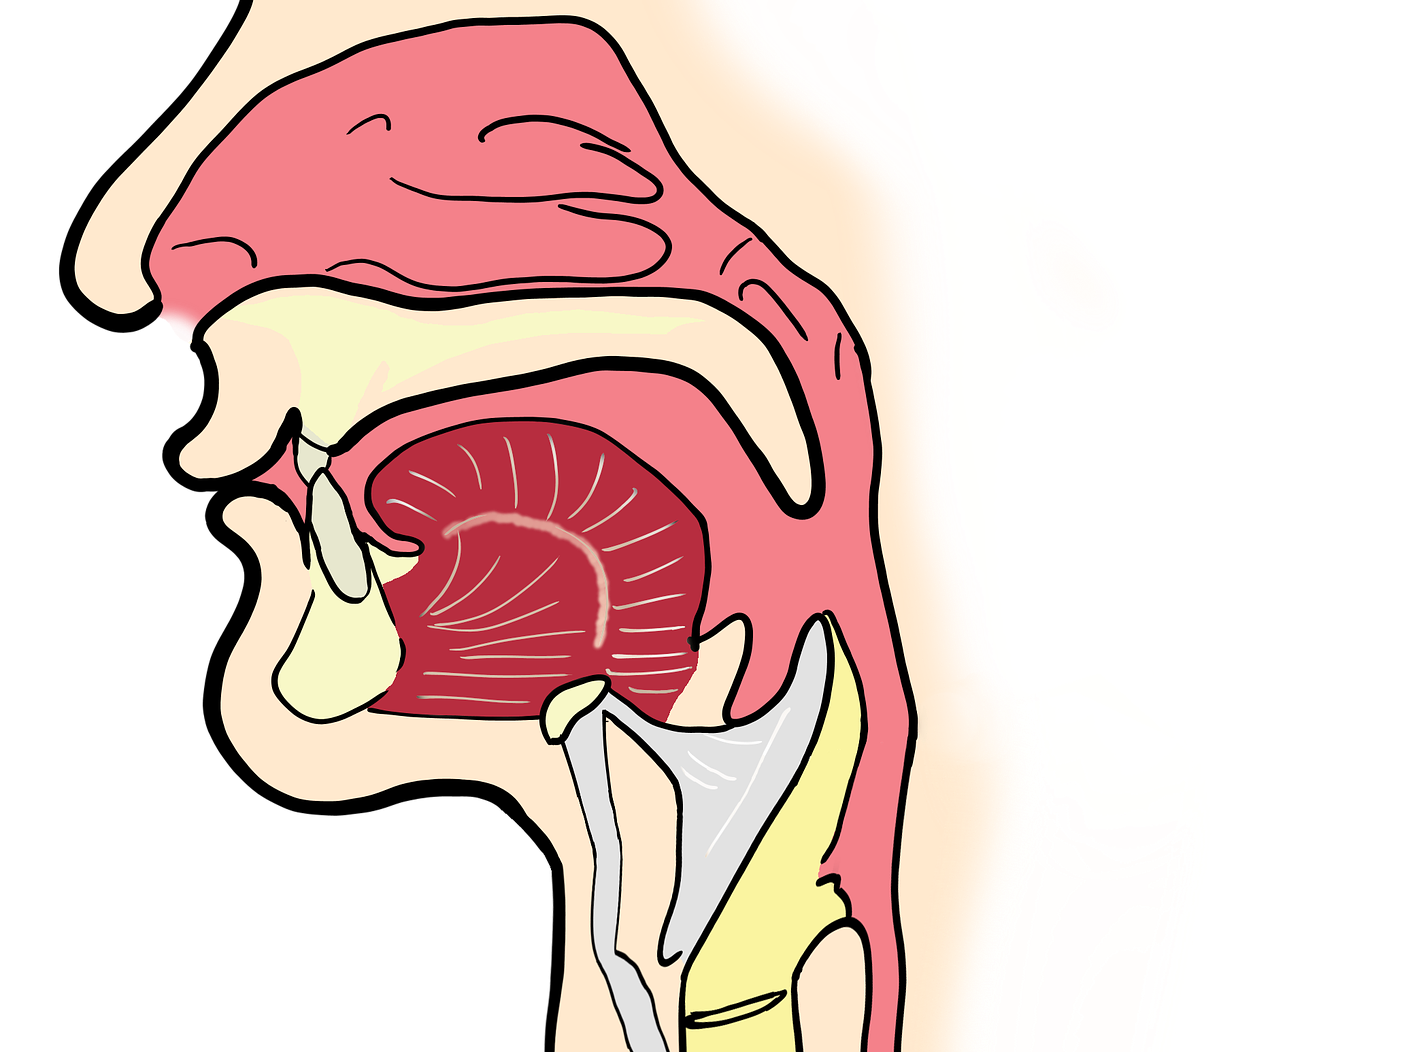

Aber eigentlich kein Wunder, wenn man sich mal betrachtet, worin unsere Sprech- und Schluckvorrichtung anatomisch eingebettet ist.

Am naheliegendsten ist dabei vermutlich die enge Beziehung zum Zungenbein. Die Hyoglossusmembran und das linguale Septum verbinden die Zunge wiederum mit den Zungenmuskeln. Die suprahyoidale (Muskeln oberhalb des Zungenbeins betreffend) Zungenaktion hilft nun, das Gleichgewicht und die Haltung des Kopfes zu stabilisieren.

Der Unterschied, den ihr vermutlich wahrgenommen habt, hat damit zu tun, dass die Zunge in enger Beziehung zum zentralen und peripheren Nervensystem steht. Infolgedessen kann man mit der Zungenhaltung Einfluss auf die Arbeit von Gehirn und Rückenmark nehmen.

Gut zu wissen: Die Positionierung der Zunge im Mund ist eine komplexe neurologische Aktivität. Dieser Prozess wird maßgeblich von bestimmten Kernen im Hirnstamm gesteuert, die wiederum Signale über die Hirnnerven an die Zungenmuskeln übertragen. Für die motorische Innervation der Zunge sind gleich drei Hirnnerven, V3 (N. mandibularis, ein Teilnerv des N. trigeminus), X (N. vagus) und XII (N. hypoglossus), zuständig. Vier, wenn man den N. facialis (VII) auch noch dazurechnet.

Interessant ist, dass sensorische Informationen von der Zunge über die Hirnnerven V, IX (N. glossopharyngeus) und X nicht, wie üblich, über den Hirnstamm im Gehirn verlaufen. Stattdessen werden sie auf der Ebene der oberen Halswirbelsäulensegmente über spezielle Neuronen weitergeleitet. Diese enge anatomische Verbindung lässt die Bewegungen der Zunge und die Bewegungen der Halswirbelsäule auf funktionelle Weise verschmelzen. „Dies ist besonders relevant bei manuellen medizinischen Behandlungen, bei denen die seitlichen Bewegungen der Zunge in der Mundhöhle in Verbindung mit der Bewegung der Halswirbelsäule therapeutisch genutzt werden können“ (Wagner, 2022). Auch kann dadurch nachvollzogen werden, warum Patienten bei Blockierungen der oberen HWS häufig ein Globusgefühl beklagen (ebd.).

Die Antwort ist ganz einfach: Das vordere Zungendrittel ruht knapp hinter den oberen Schneidezähnen am Gaumen. Die Zungenspitze drückt dabei nicht gegen die Schneidezähne. Das ist die Zungenruheposition.